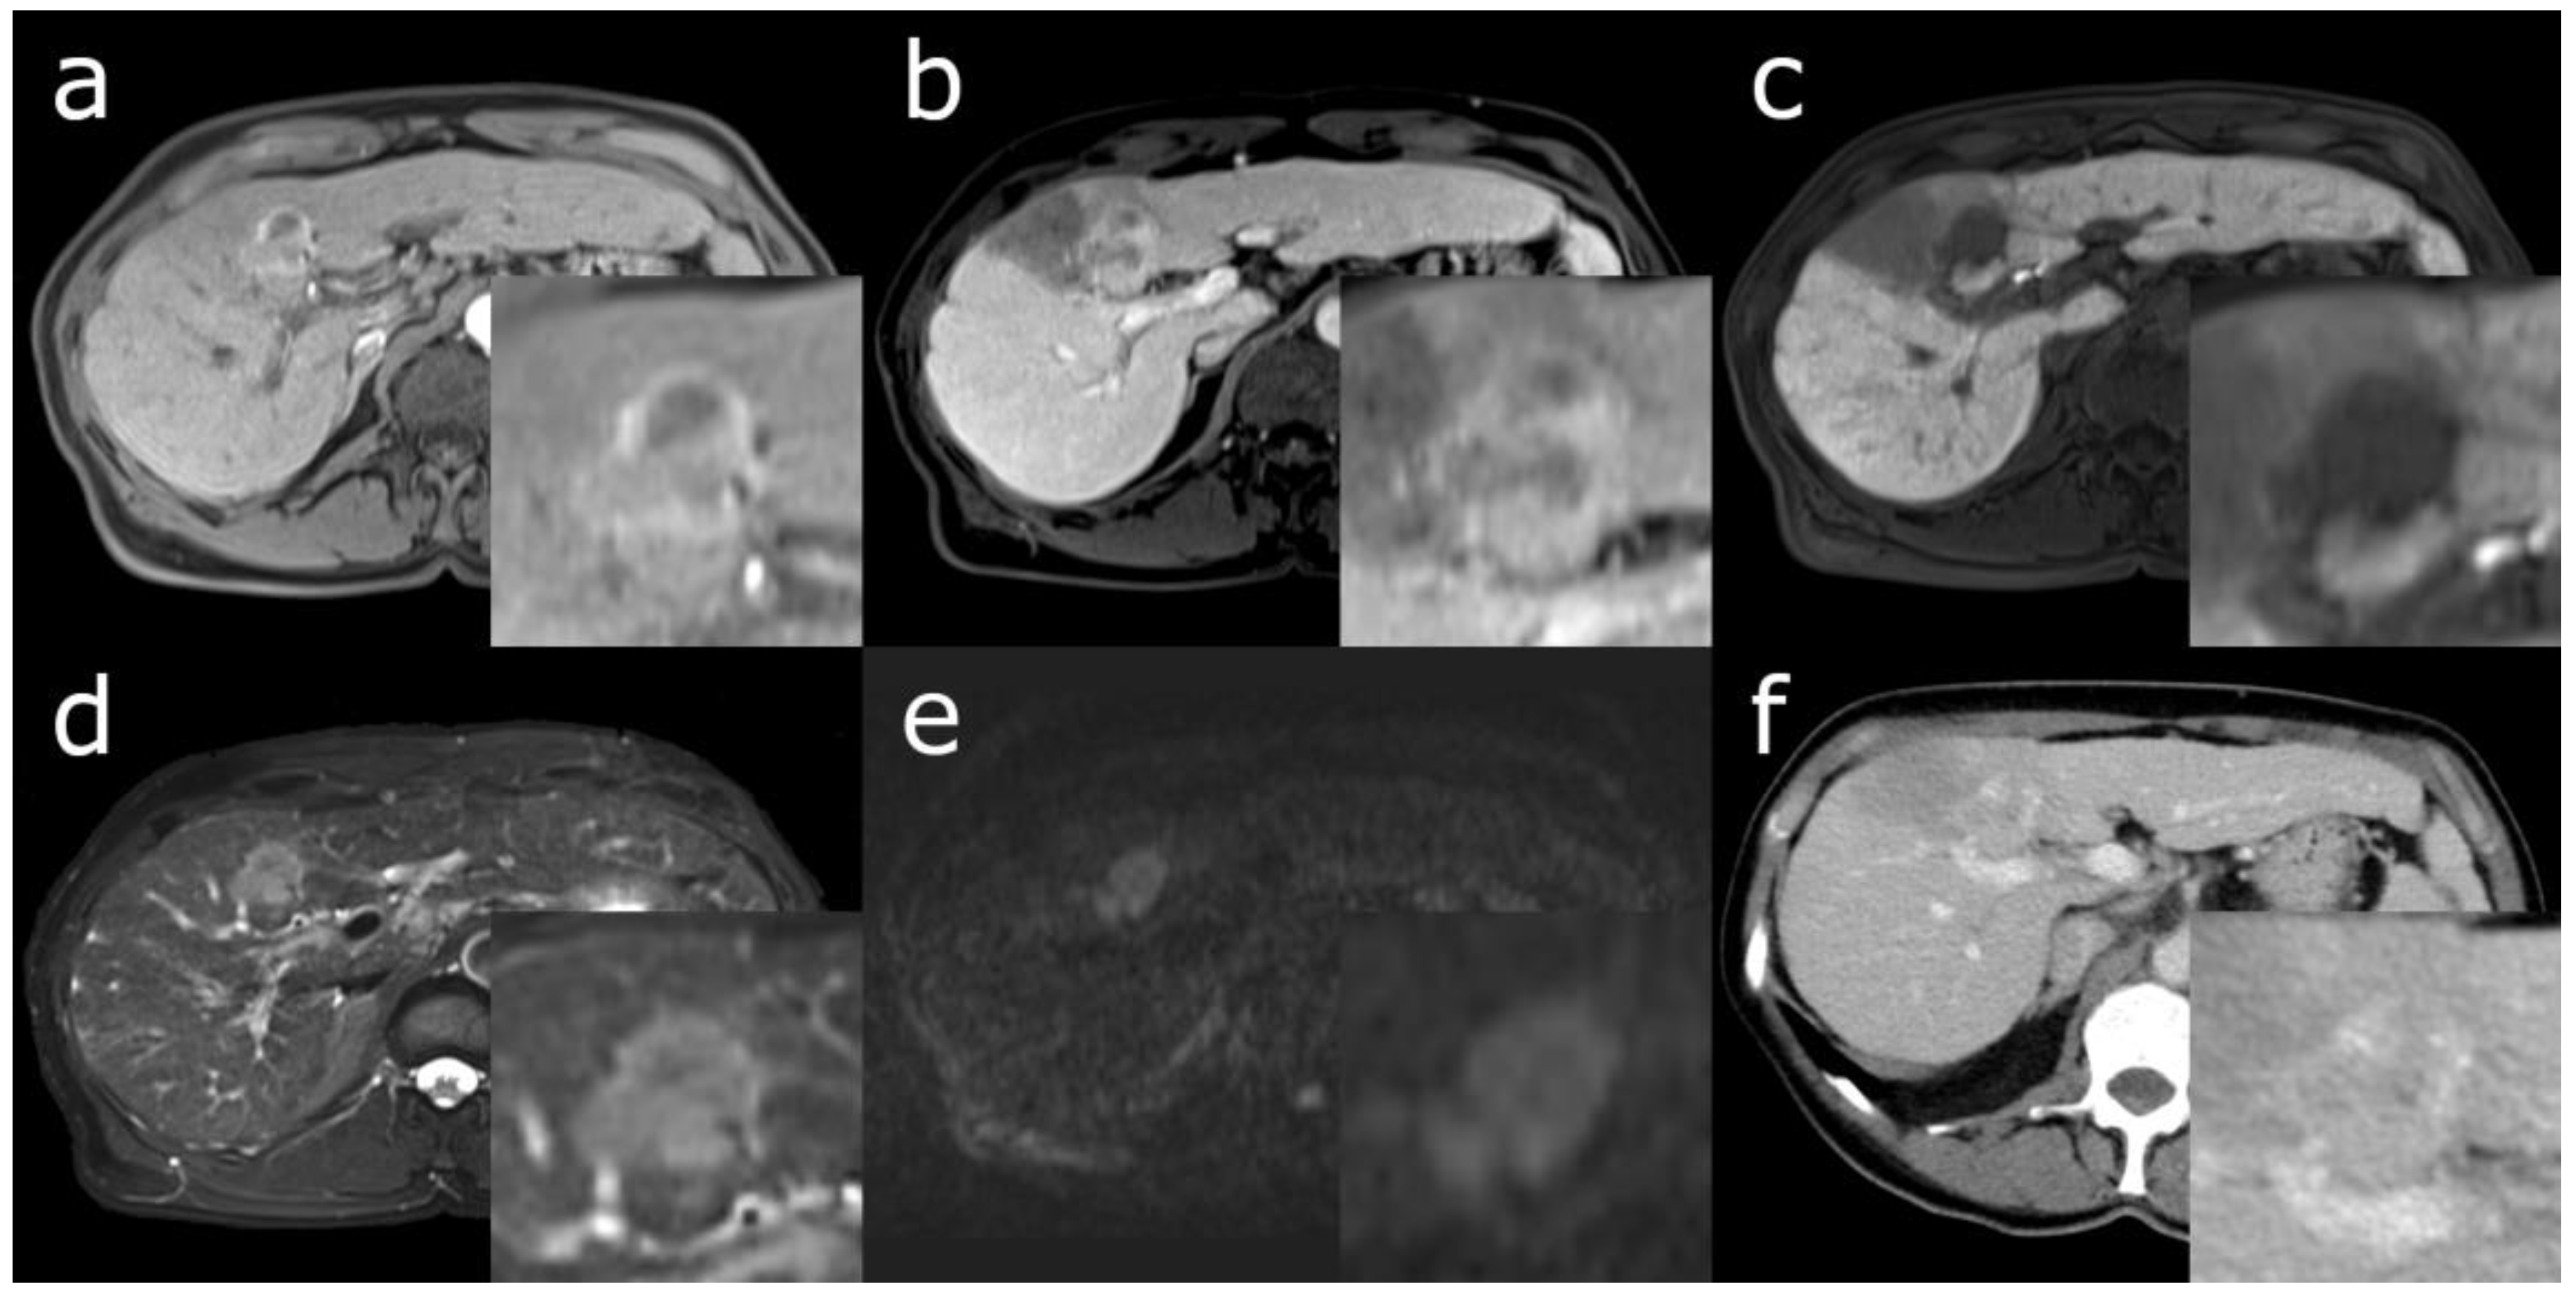

- Park, S.H.; Lee, S.S.; Yu, E.; Kang, H.J.; Park, Y.; Kim, S.Y.; Lee, S.J.; Shin, Y.M.; Lee, M.G. Combined hepatocellular-cholangiocarcinoma: Gadoxetic acid-enhanced MRI findings correlated with pathologic features and prognosis. J. Magn. Reson. Imaging 2017, 46, 267–280. [Google Scholar] [CrossRef]

- Choi, S.H.; Jeon, S.K.; Lee, S.S.; Lee, J.M.; Hur, B.Y.; Kang, H.J.; Kim, H.; Park, Y. Radio-pathologic correlation of biphenotypic primary liver cancer (combined hepatocellular cholangiocarcinoma): Changes in the 2019 WHO classification and impact on LI-RADS classification at liver MRI. Eur. Radiol. 2021, 31, 9479–9488. [Google Scholar] [CrossRef]

- Fowler, K.J.; Sheybani, A.; Parker, R.A., 3rd; Doherty, S.; E, M.B.; Chapman, W.C.; Menias, C.O. Combined hepatocellular and cholangiocarcinoma (biphenotypic) tumors: Imaging features and diagnostic accuracy of contrast-enhanced CT and MRI. AJR Am. J. Roentgenol. 2013, 201, 332–339. [Google Scholar] [CrossRef] [PubMed]

- Chi, C.T.; Chau, G.Y.; Lee, R.C.; Chen, Y.Y.; Lei, H.J.; Hou, M.C.; Chao, Y.; Huang, Y.H. Radiological features and outcomes of combined hepatocellular-cholangiocarcinoma in patients undergoing surgical resection. J. Formos. Med Assoc. 2020, 119, 125–133. [Google Scholar] [CrossRef] [PubMed]

- Sagrini, E.; Iavarone, M.; Stefanini, F.; Tovoli, F.; Vavassori, S.; Maggioni, M.; Renzulli, M.; Salvatore, V.; Stefanescu, H.; Colombo, M.; et al. Imaging of combined hepatocellular-cholangiocarcinoma in cirrhosis and risk of false diagnosis of hepatocellular carcinoma. United Eur. Gastroenterol. J. 2019, 7, 69–77. [Google Scholar] [CrossRef]